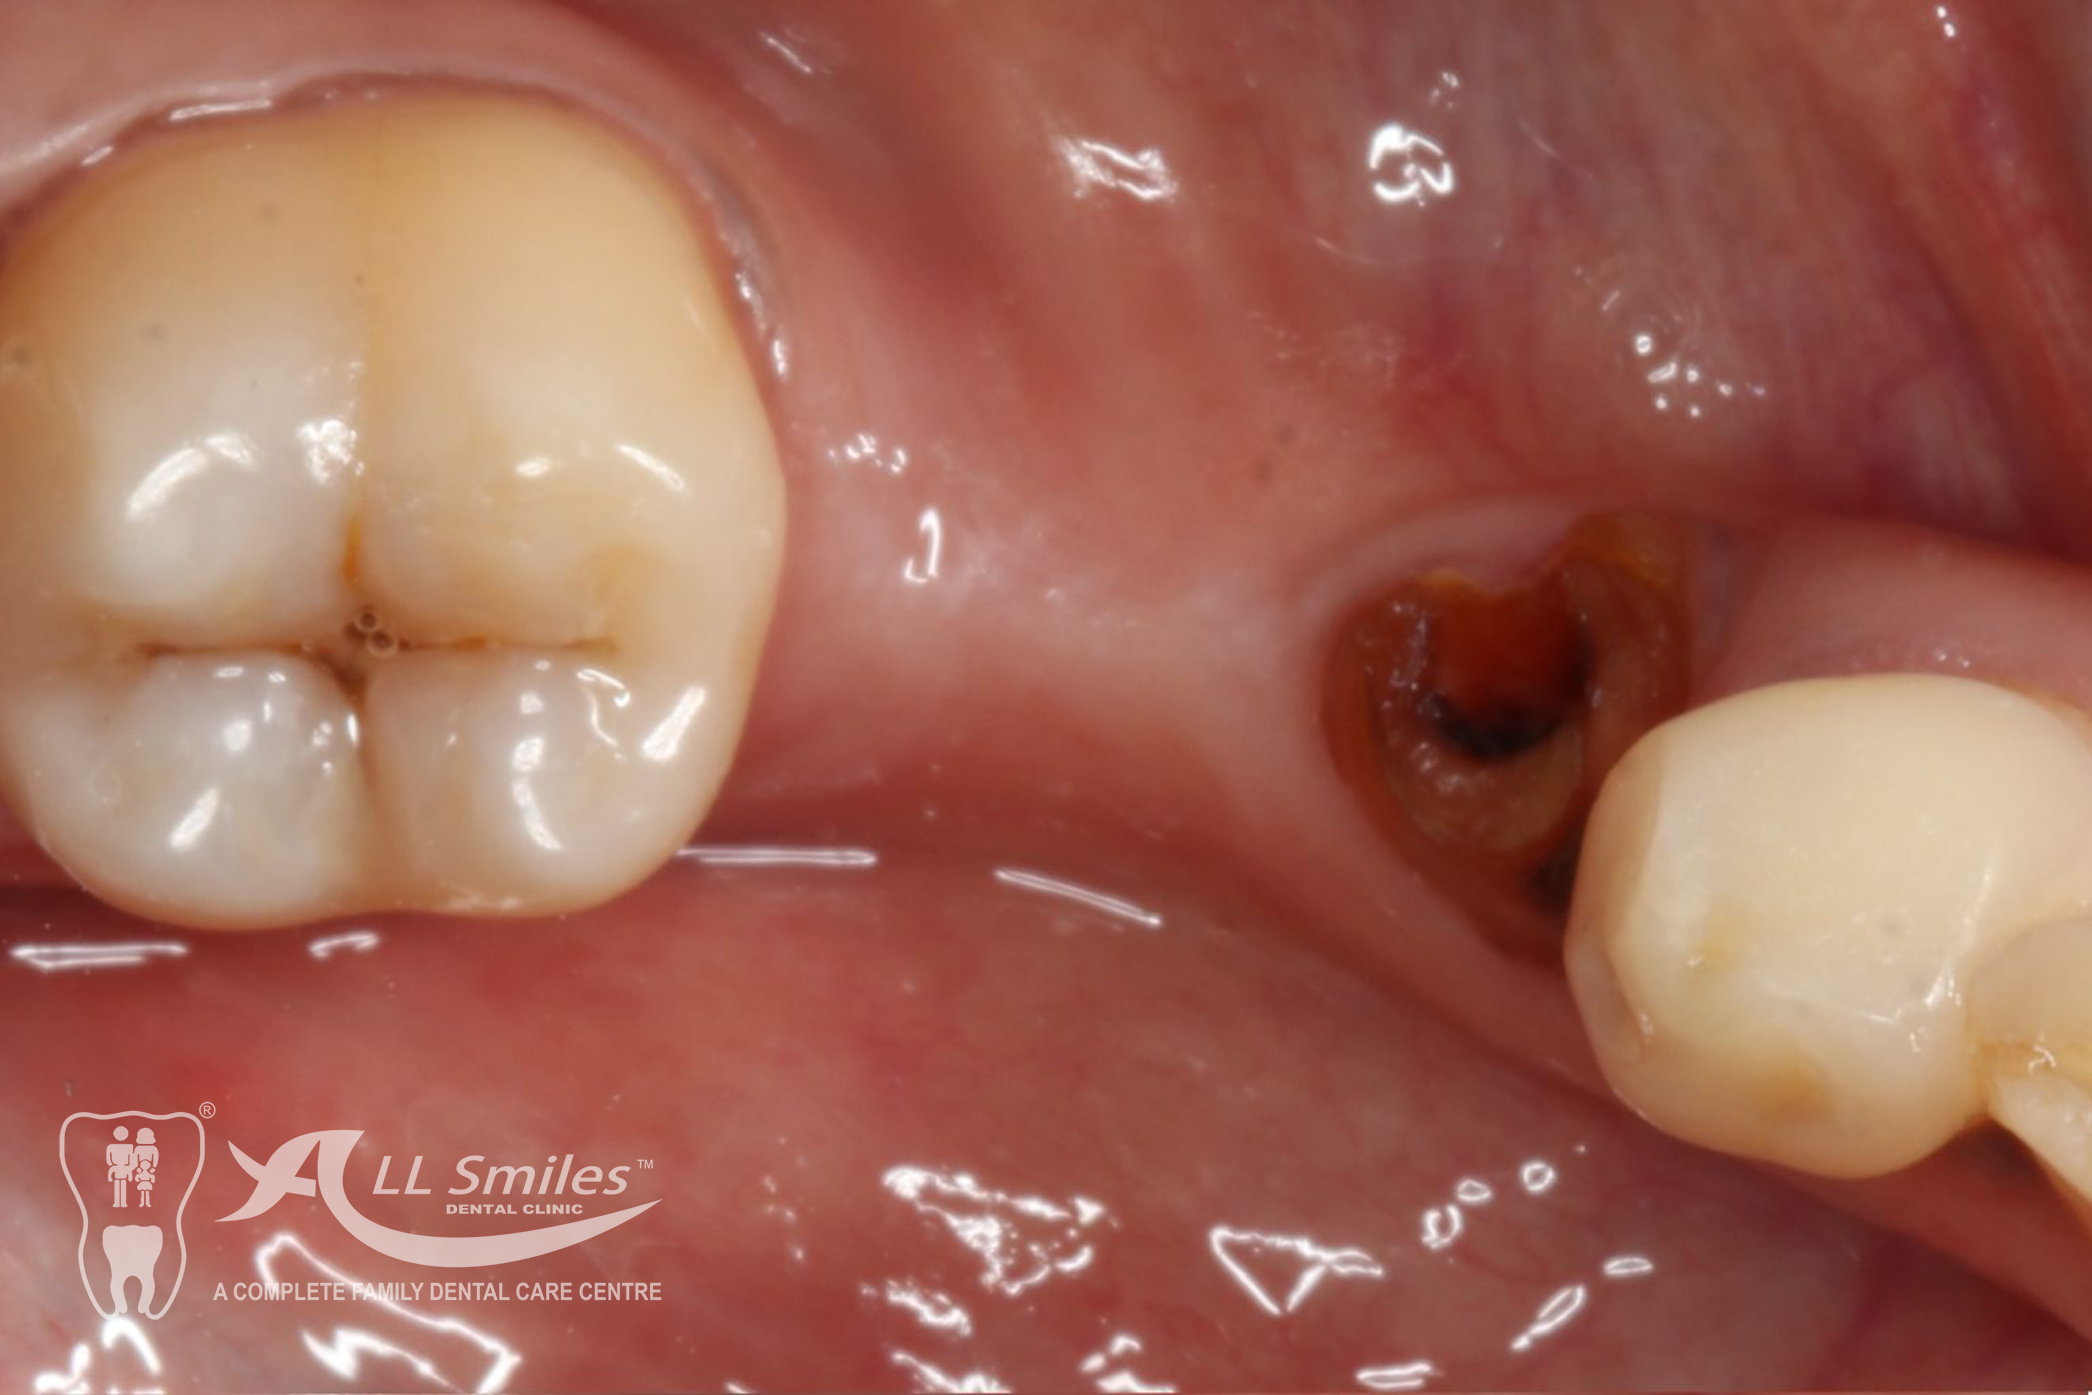

Crowns & Bridges Gallery